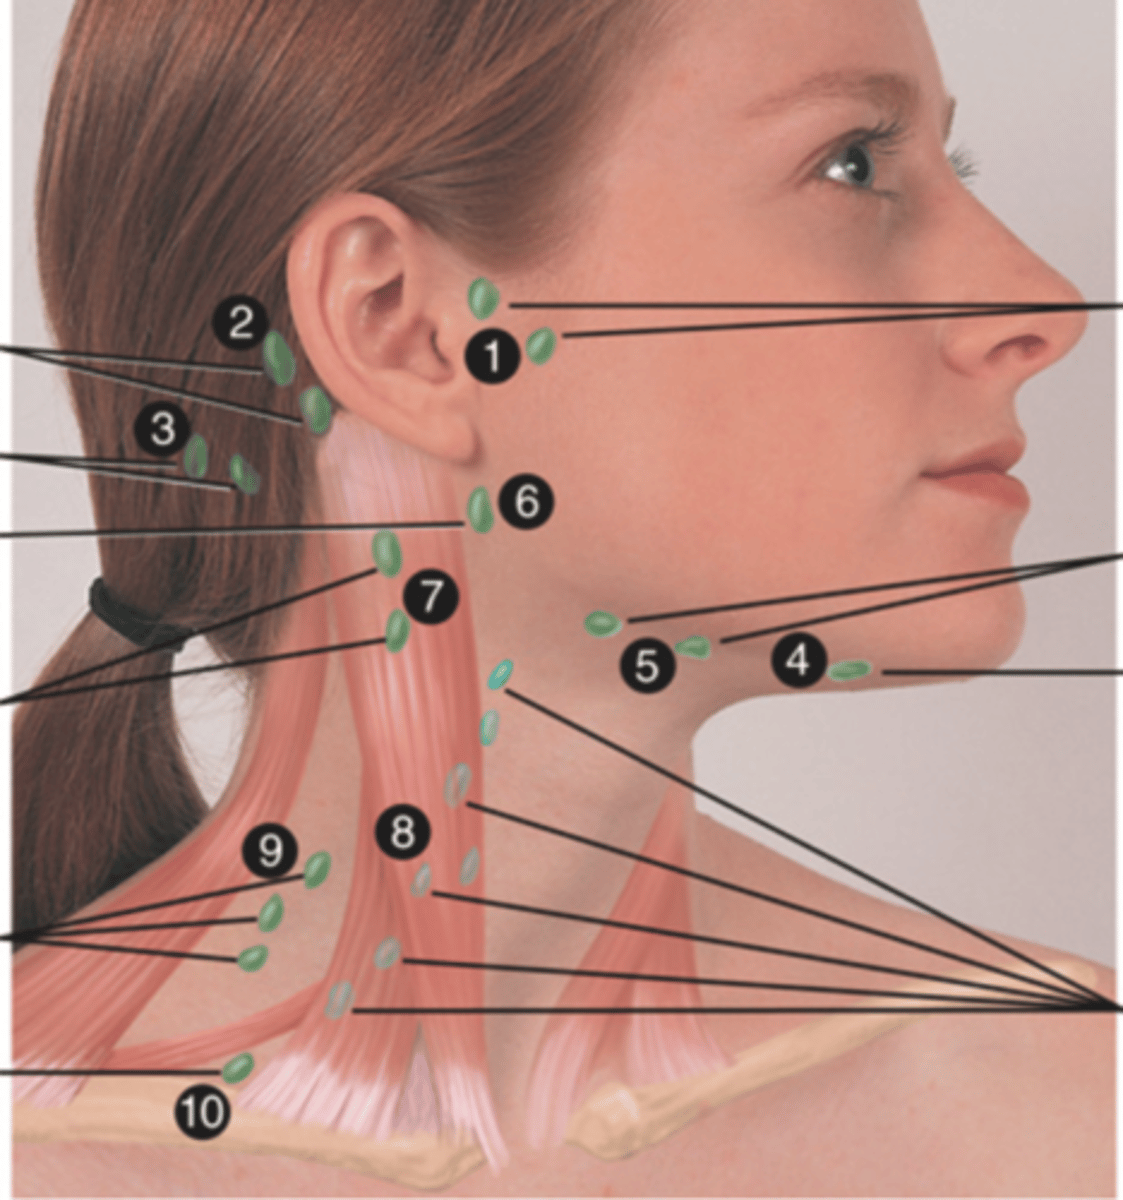

Major Lymph Nodes in the Neck (FUN!)

(Party People Often Sell Sardines Just So Dogs Pee Silver)

Preauricular Lymph Node

Lymph node in front of the ear (1)

Posterior Auricular Lymph Node

Lymph node behind the ear (2)

Occipital Lymph Node

Lymph node at the base of skull (3)

Submental Lymph Node

Lymph node under the chin (4)

Submandibular Lymph Node

Lymph node along base of mandible (5)

Jugulodigastric (Tonsil) Lymph Node

Lymph node under the angle of the mandible (6)

Superficial Cervical Lymph Node

Lymph node overlying the sternomastoid muscle (7); can feel enlarged even when there are no problems

Deep Cervical Chain Lymph Node

Lymph node located on the posterior triangle of the neck (8)

Posterior Cervical Lymph Node

Lymph node in the posterior triangle along the edge of the trapezius muscle (9)

Supraclavicular Lymph Node

Lymph node just above and behind the clavicle, at the sternomastoid muscle (10)